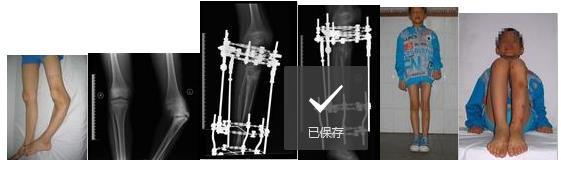

先天性胫内翻畸形在我科经Ilizarov外固定支架矫形及胫骨延长后,畸形矫正,双下肢等长功能良好。

利用Ilizarov外固定支架矫正大龄马蹄内翻足

外伤性外踝缺损伴踝外翻 使支架后用俄罗斯外固定支架治疗后恢复正常。